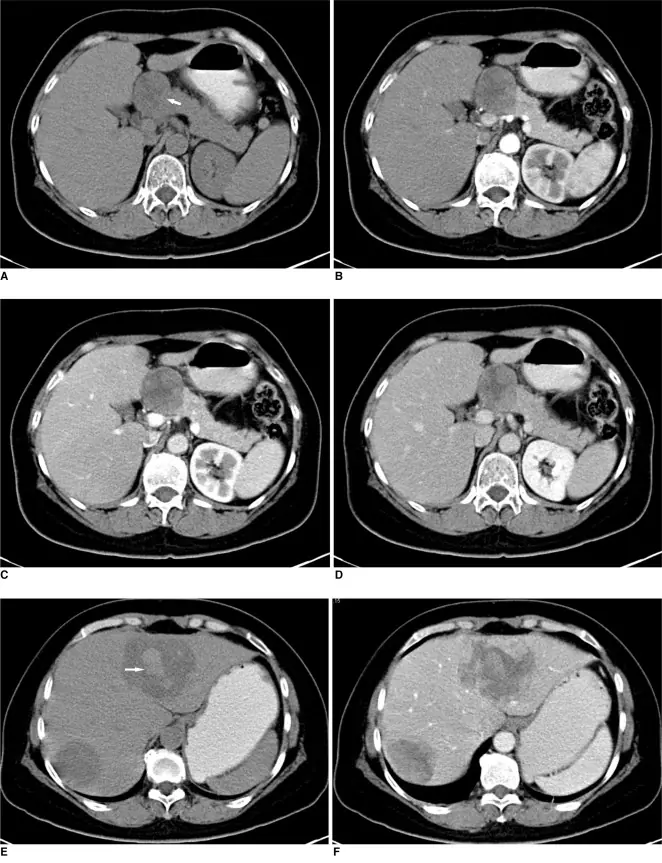

一名 57 歲女性因上腹部腫塊被送入醫院進一步評估,該腫塊在體檢時腹部超音波檢查中偶然被發現。患者出現反覆腹脹,無其他症狀。她的病史平常,除了兩年前診斷出膽囊菌石症和脂肪肝以外,並無特別異常。入院時,身體檢查顯示輕微肝擊痛,但未觸診腫塊。實驗室檢測顯示α胎兒蛋白(AFP)> 35,350 ng/ml(參考:< 20 ng/ml)含量極高。CA19-9、CA125、血液澱粉酶、天冬氨酸轉移酶(AST)、丙氨酸轉移酶(ALT)及膽紅素水準均在正常範圍內。在靜脈注射顯影劑後,進行了腹部對比劑前及增強螺旋的電腦斷層檢查,包括動脈期、門脈期及平衡期。電腦斷層顯示胰臟頸部及本體有一個直徑 4.5 公分、邊緣平滑、孤立且異質的腫塊( 見圖 A)。在顯影後電腦斷層之影像中,腫塊呈現中度不均勻增強,伴隨中央低衰減( 圖 B-D)。肝臟發現兩個低密度病灶,分別測量為 4.7×4.3 公分及 7.0×6.8 公分,顯示出極少的彌漫性異質增強( 圖 1E、F)。左側肝葉大塊高密度顯示為腫塊內有中心性出血。

由於胰臟卵黃囊腫瘤是極為稀有,手術前要診斷出胰臟卵黃囊腫瘤是極為較為困難。血清腫瘤指數的AFP數值會顯著上升,這成為可能診斷的線索。胰臟卵黃囊腫瘤的電腦斷層影像發現常是大而光滑、邊緣良好、增強良好的固體腫塊,並帶有囊性、出血或壞死部分。內視鏡超音波引導的細針抽吸可能是胰臟卵黃囊腫瘤的有效診斷方式,切片標本的組織病理學可提供明確診斷。